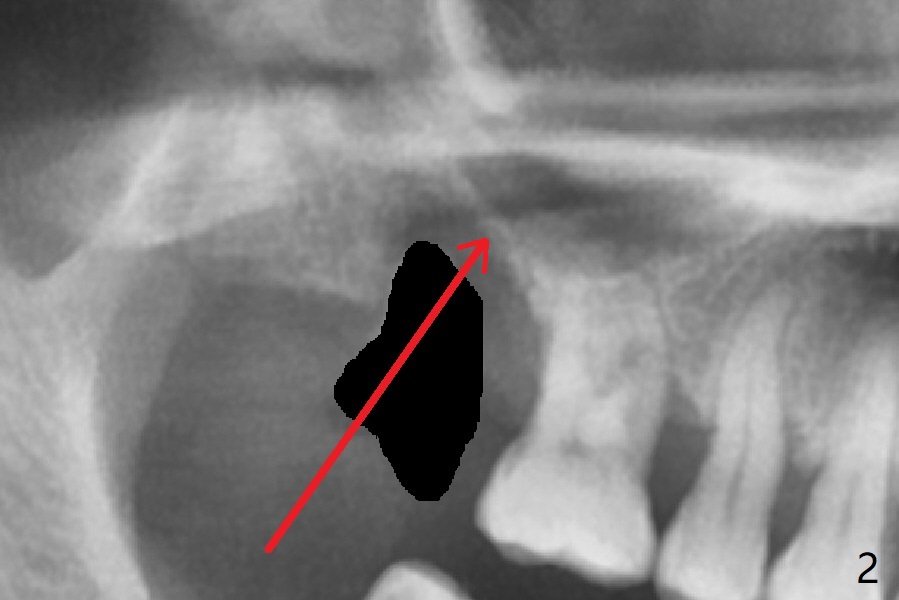

After extraction of the tooth #2 (Fig.1), osteotomy is supposed to be initiated in the mesial slope (Fig.2 arrow). With Magic Expanders (3-4.8 mm), osteotomy ends up in the bottom of the socket (Fig.3). Trajectory is found to be off when 4x9 and 5x9 mm dummy FC implants are placed with stability (Fig.4,5). The final implant, Magicore (5x7(3)mm, >29 Ncm), appears to be placed too deep for restoration (Fig.6,7); a screw retained crown may be a solution. PRF membrane and Vanilla (allograft) are used for sinus lift (no sinus membrane perforation). Following Vanilla graft in the socket gap (Fig.6 *), another piece of PRF membrane is used to cover socket opening. The membrane is fixed in place with suture and periodontal dressing. The implant seems to have osteointegrated 3.5 months postop (Fig.8). After change to 4.3x5 mm solid abutment and mesial surface adjustment, impression is taken for early loading because of removal of #14 implant. In fact the patient is satisfied with mastication improvement at #2 later on.